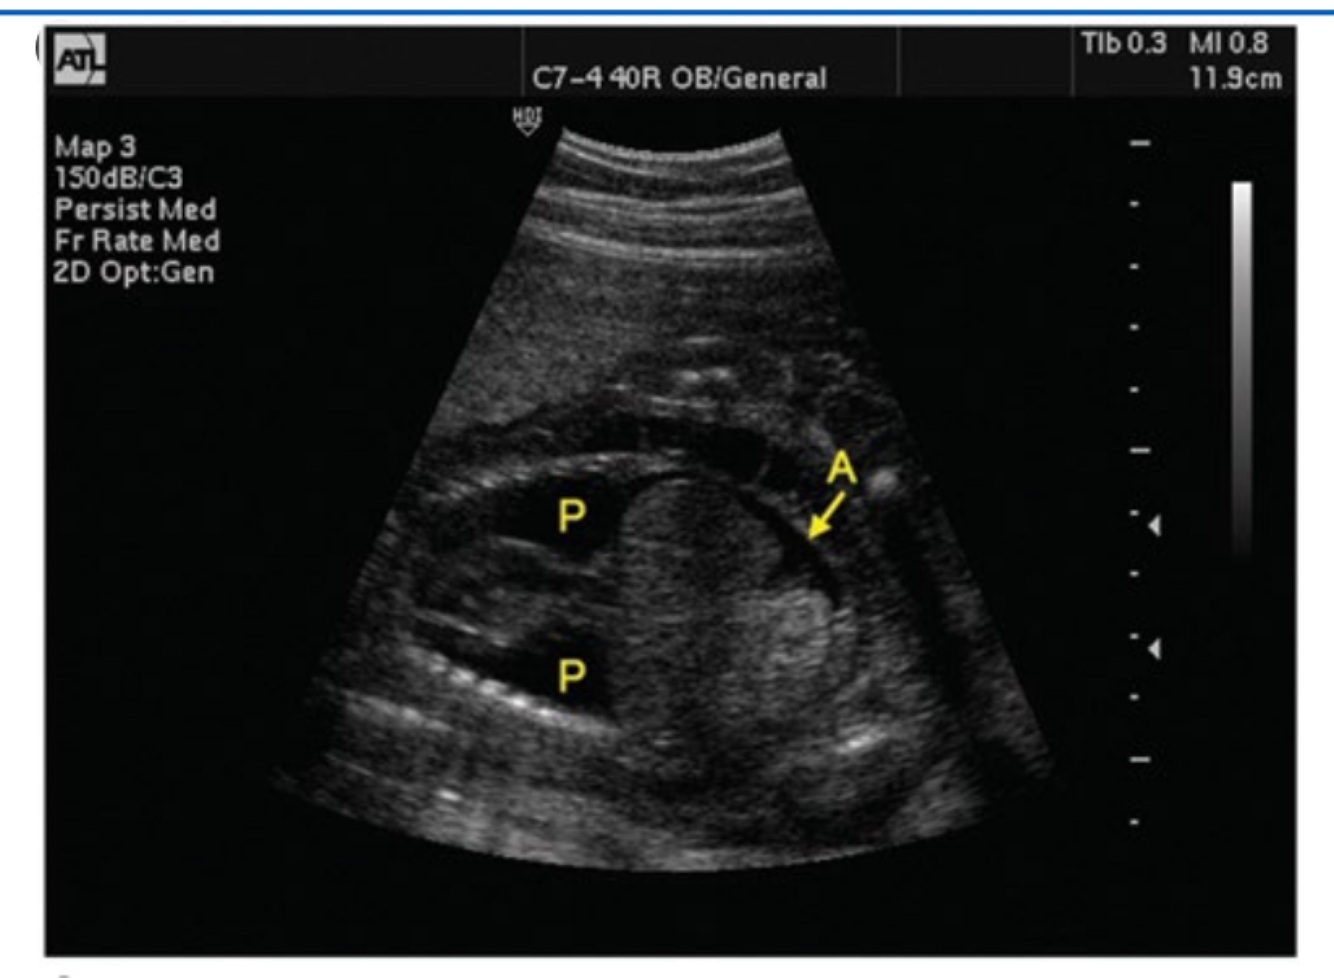

What does this image demonstrate?

One body cavity with edema